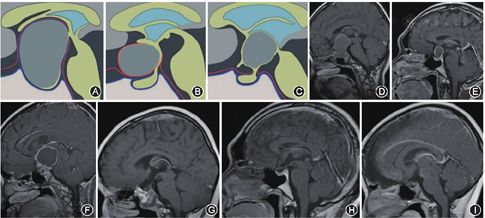

通过前期成人及胎儿标本的解剖学研究,基于肿瘤起源位置和周边膜性结构关系的QST分型[3,4](图1):Q型:起源于鞍隔下的垂体中间叶或垂体柄鞍膈下段,当通过鞍膈孔凸向鞍上时,可有雪人症。肿瘤主体多位于鞍内,可见蝶鞍扩大,甚至凸向海绵窦,鞍膈或部分鞍膈向上膨隆。即使肿瘤较大,周边仍可见鞍膈孔及基底蛛网膜,垂体柄中上段完整存在。S型:起源于鞍膈上垂体柄袖套外及袖套间段,位于鞍膈上,有部分外层蛛网膜和内层蛛网膜与结节漏斗部相隔。肿瘤位于蛛网膜腔内生长,肿瘤可将鞍膈向下推移或不变,垂体清晰可见,三脑室底部向上推移,矢状正中位多可见结节漏斗部和垂体柄。可分为累及多个脑池的肿瘤和只累及单个脑池的肿瘤。当鞍膈孔较大时,肿瘤可部分凸入鞍内生长,但蝶鞍不扩大,鞍内的神经垂体和腺垂体多清晰可见,可见鞍膈和基底蛛网膜大部分完整,位于肿瘤下方。T型:起源于垂体柄袖套内段疏松部、结节漏斗部,肿瘤通过三脑室底凸出卷向三脑室底内或蛛网膜内生长,结节漏斗部正中结构被推挤变形,难以辨认,三脑室内膜延续于肿瘤上方,三脑室底内层蛛网膜及liliequest膜的间脑叶将肿瘤与脚间池相隔。当liliequest膜稀疏或呈网状时,可凸入脚间池生长。垂体柄中下段多存在,当肿瘤穿垂体柄生长时,垂体柄呈喇叭样扩张。该型由于个体间相关蛛网膜结构的差异,肿瘤的生长方式及影像学表现多样,但肿瘤下极与神经血管间存在着多量的内层蛛网膜及完整的基底蛛网膜。